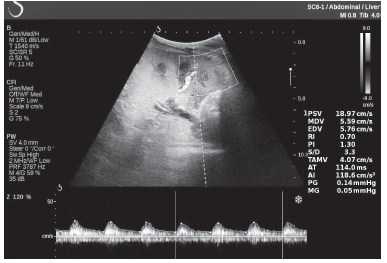

Клинический пример из второй группы. Пациент К. перенес операцию пересадки почки от живого родственного донора. Трансплантат в левой подвздошной области. Индекс резистентности в междольковых артериях составил 0,70 (рис. 5). В сегментарных артериях индекс резистентности составил 0,66 (рис. 6). Показатели жесткости паренхимы почечного трансплантата при режиме УЭСВ составили от 31,6 до 36,9 кПа (рис. 7-9).

Рисунок 6. Эхограмма пациента К. Кровоток в сегментарных артериях неизменен